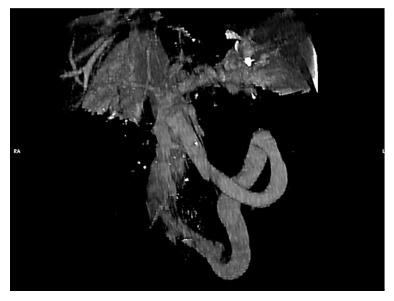

Disabling portosystemic encephalopathy in a non-cirrhotic patient: Successful endovascular treatment of a giant inferior mesenteric-caval shunt the left internal iliac vein.

Hepatic encephalopathy is suspected in non-cirrhotic cases of encephalopathy because the symptoms are accompanied by hyperammonaemia. Some cases have been misdiagnosed as psychiatric diseases and consequently patients hospitalized in psychiatric institutions or geriatric facilities. Therefore, the importance of accurate diagnosis of this disease should be strongly emphasized. A 68-year-old female patient presented to the Emergency Room with confusion, lethargy, nausea and vomiting. Examination disclosed normal vital signs. Neurological examination revealed a minimally responsive woman without apparent focal deficits and normal reflexes. She had no history of hematologic disorders or alcohol abuse. Her brain TC did not demonstrate any intracranial abnormalities and electroencephalography did not reveal any subclinical epileptiform discharges. Her ammonia level was > 400 mg/dL (reference range < 75 mg/dL) while hepatitis viral markers were negative. The patient was started on lactulose, rifaximin and low-protein diet. On the basis of the doppler ultrasound and abdomen computed tomography angiography findings, the decision was made to attempt portal venography which confirmed the presence of a giant portal-systemic venous shunt. Therefore, mechanic obliteration of shunt by interventional radiology was performed. As a consequence, mesenteric venous blood returned to hepatopetally flow into the liver, metabolic detoxification of ammonia increased and hepatic encephalopathy subsided. It is crucial that physicians immediately recognize the presence of non-cirrhotic encephalopathy, in view of the potential therapeutic resolution after accurate diagnosis and appropriate treatments.